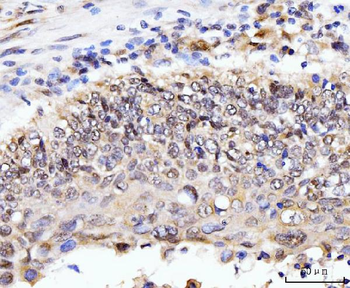

AKAP8 Antibody

| Description | AKAP8 Antibody |

| Tested applications | IHC |

| Reactivity | Human |

| Dilution range | IHC: 1/20-1/100 |